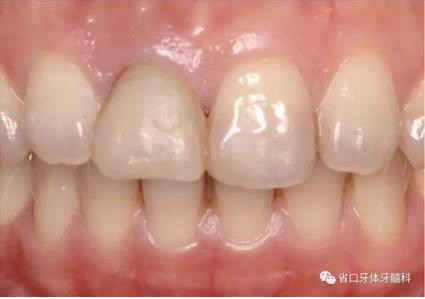

圖1 術(shù)前口內(nèi)照

圖2 術(shù)前口內(nèi)照

圖3 術(shù)前口內(nèi)照